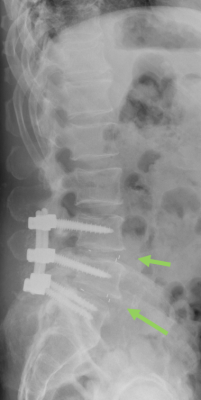

Stabilisierende Operationen

Zeigt sich ein höhergradiger Verschleiß bzw. eine ausgeprägte Instabilität, wird der betroffene Wirbelsäulenabschnitt versteift (Fusion). Kombiniert mit diesem Verfahren kann ggf. auch eine Erweiterung des Wirbelkanals (Dekompression) bei Verengung (Spinalstenose) erfolgen.